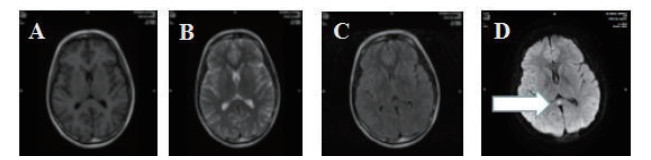

磁共振提示胼胝体局灶病变多为轻症患者(图 3);磁共振提示胼胝体双侧放射冠部散在病变多为中型患者(图 4);磁共振提示胼胝体双侧放射冠区弥漫性病变多为重症患者(图 5,6)。

| 图 6 重型患者,可见胼胝体双侧放射冠区弥漫性病变 |